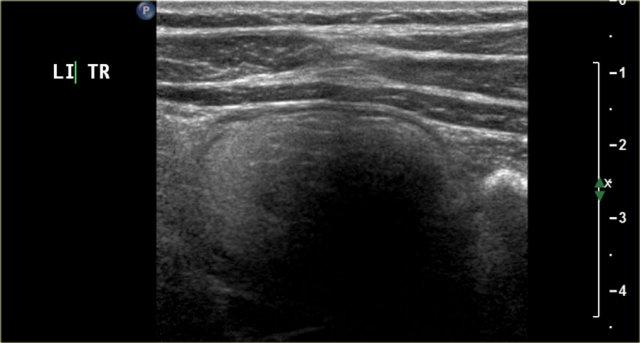

Một bé trai 1 tuổi được chuyển đến với chẩn đoán u nguyên bào thận dạng nang.

Siêu âm phát hiện một nang lớn ở trung tâm ổ bụng.

Khi khảo sát từ hông trái bằng đầu dò tuyến tính tần số cao, có thể thấy một ít mô nhu mô bao quanh các đài thận giãn rất to. Hình ảnh này phù hợp với ứ nước thận mức độ nặng.

Ban đầu, người ta cho rằng có một số thành phần đặc trong nang.

Tuy nhiên, khi ấn đầu dò, các thành phần này được xác định là cặn lắng.

MRI cho thấy hình ảnh tổng quan hơn về tình trạng ứ nước thận.

Nguyên nhân là do hẹp khúc nối bể thận – niệu quản.

Thận trái có chức năng phân chia 33% trên xạ hình thận.

Phẫu thuật tạo hình bể thận đã được thực hiện thành công.